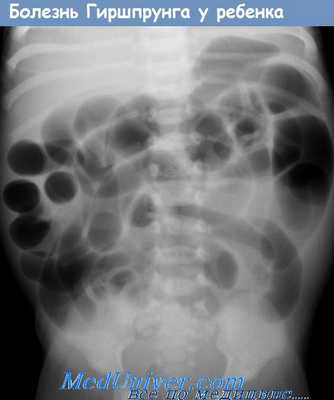

Радиологические исследования часто выполняются в первую очередь из-за их доступности и низкой инвазивности. На изображении брюшной полости видны растянутые петли толстой кишки и наличие уровней жидкости и газа.

При ректальном введении контрастного вещества виден воронкообразный участок переходной зоны – «симптом конуса» – на границе кишечника. На позднем снимке через 24 часа виден остаточный контраст в дистальной части кишечника.